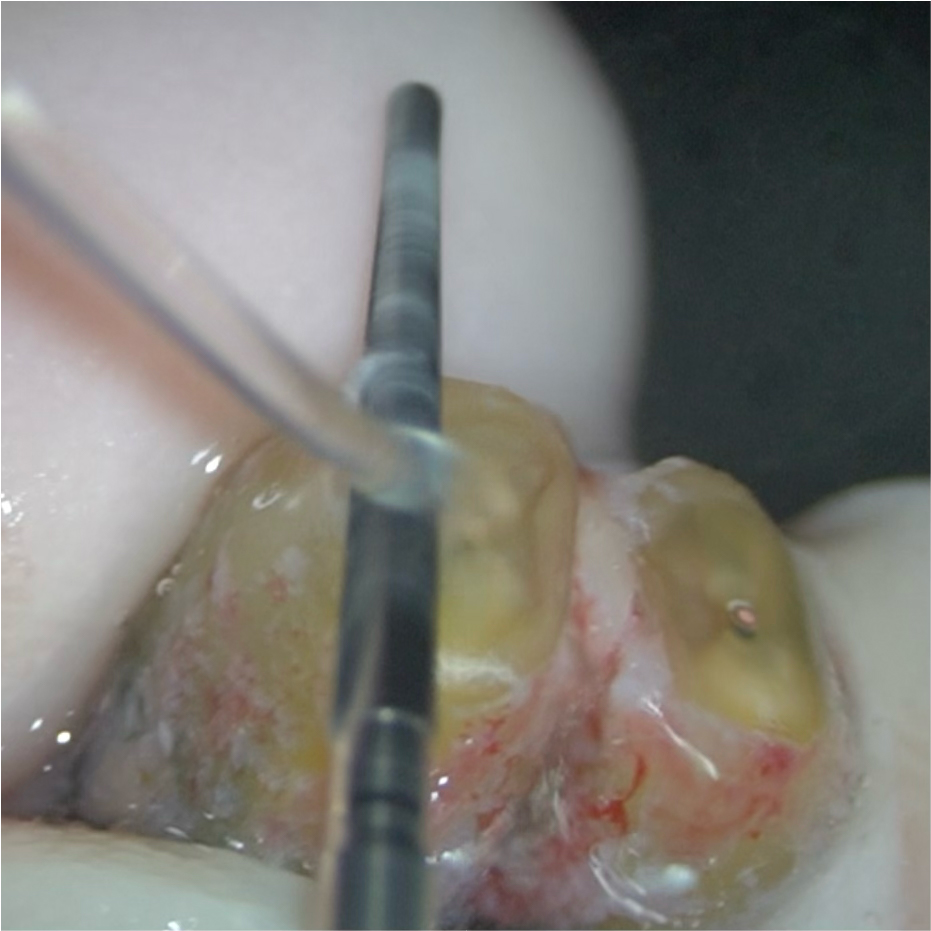

③拡大視野での精査

色素で染め出しを行い、クラックの有無や、切断面の根管の形態(複根管やイスムスなど)を精査します。この工程は、裸眼で精査することは難しく、高倍率での顕微鏡下での精査が必要です。ここでもしもわずかなクラックが認められる場合、クラックが消失するまで根尖部分の切除を進めます。